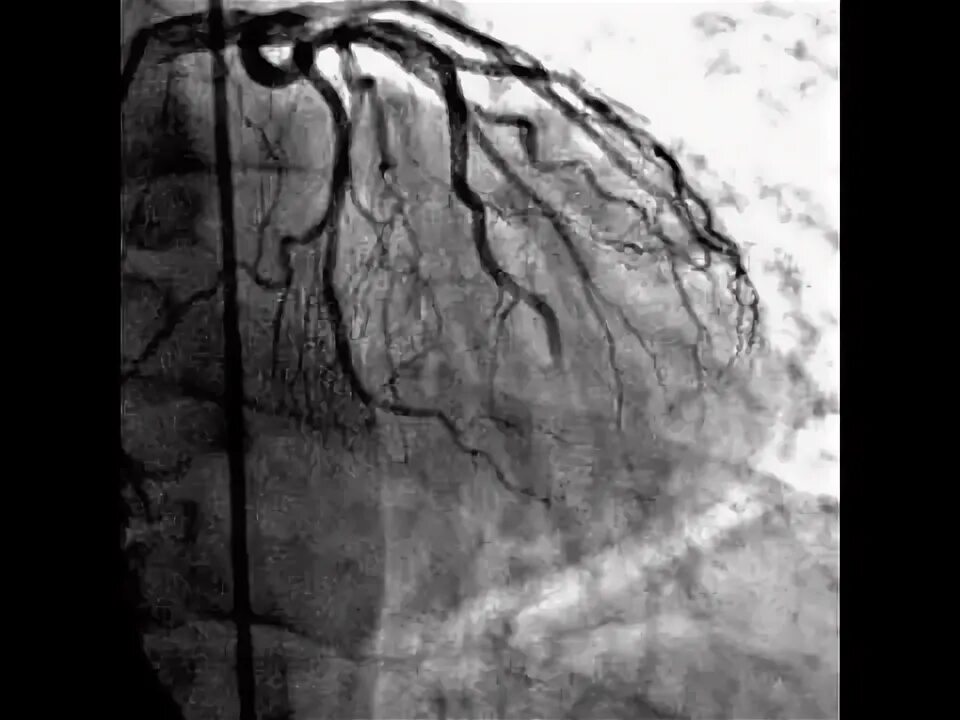

No reflow феномен